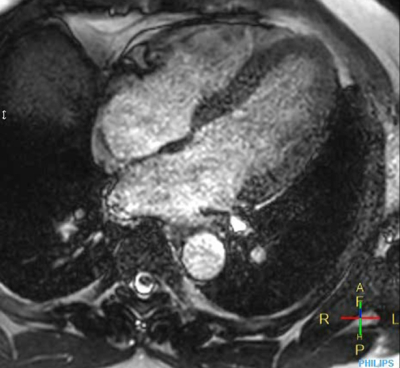

Cine 2D BFFE (4 CAV)

Elition X 3.0T

東京警察病院